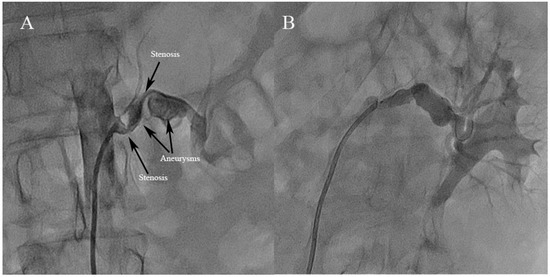

3.2. Angiographic Findings and Treatment